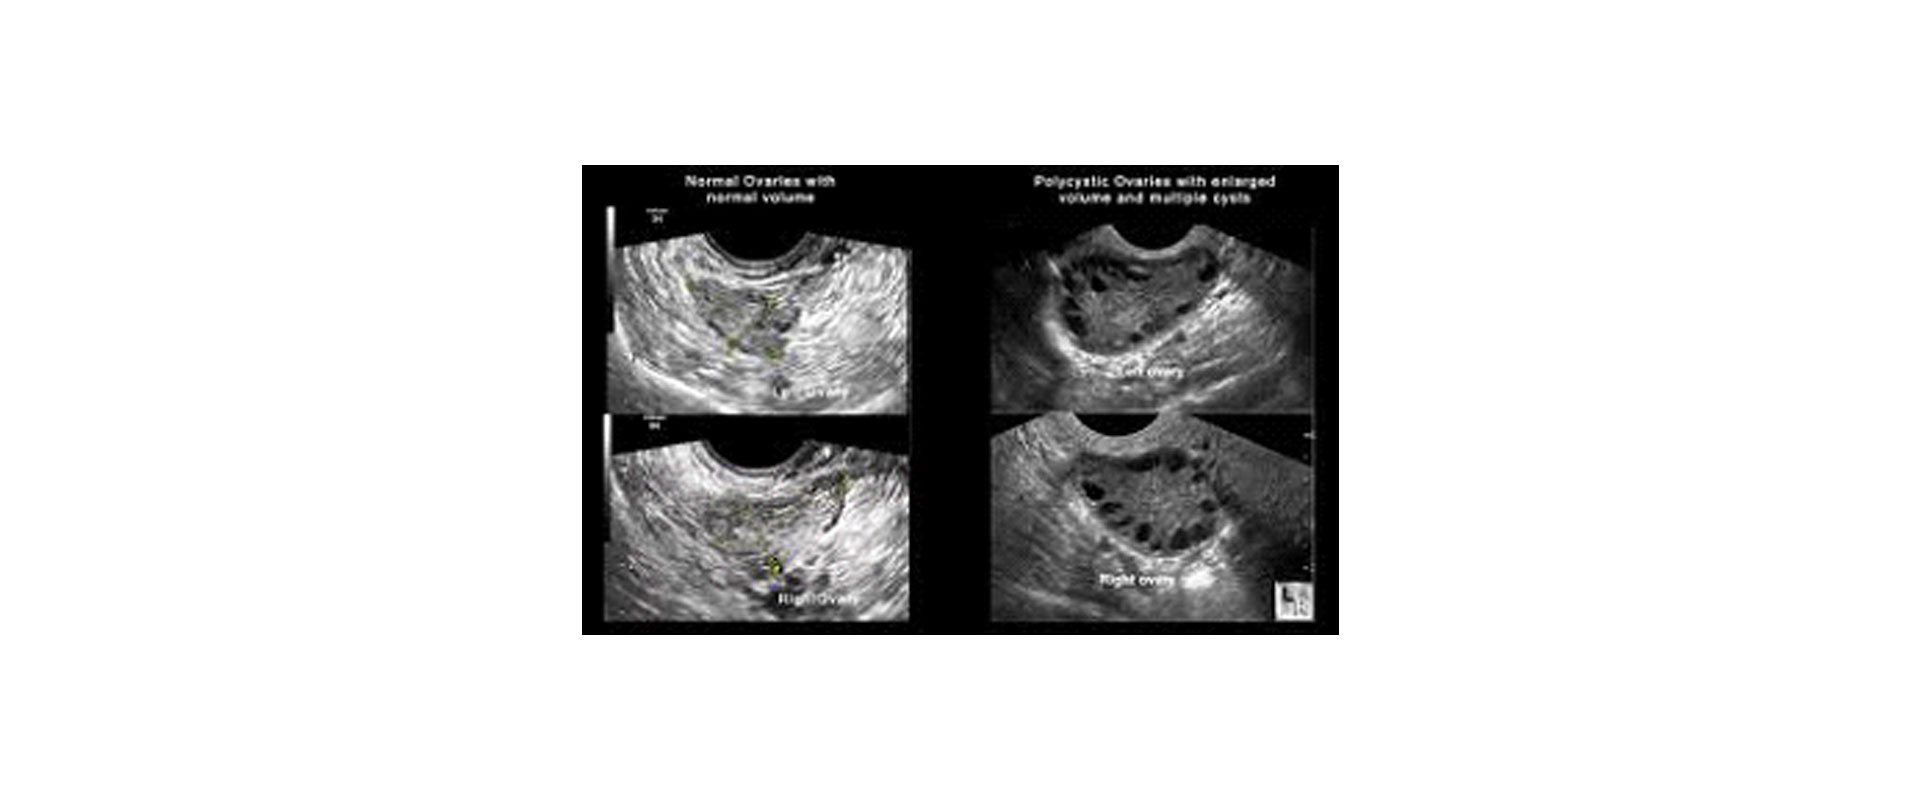

Κολπικός υπέρηχος

Η υπερηχογραφική εμφάνιση του συνδρόμου πολυκυστικών ωοθηκών χαρακτηρίζεται από διογκωμένες ωοθήκες με περισσότερες από 10 κύστεις διαμέτρου 2-8 mm σε μία υπερηχογραφική τομή και παχύ κεντρικό στρώμα. Οι κύστεις αυτές διατάσσονται περιφερικά με μορφή περιδεραίου ή διαμέσου του παχέος ηχογενούς κεντρικού στρώματος.

Για την ορθή εκτίμηση, το διακολπικό υπερηχογράφημα υπερέχει σαφώς του κοιλιακού, ενώ η υπερηχογραφική εμφάνιση είναι ο δείκτης του συνδρόμου με τη μεγαλύτερη ευαισθησία.